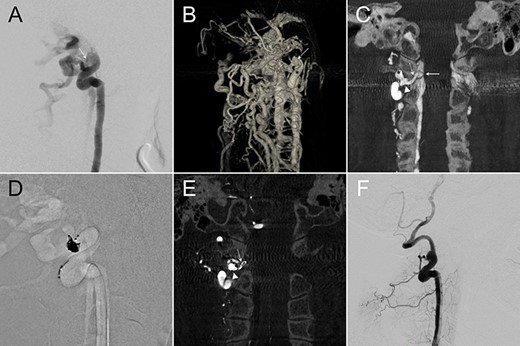

A 60-year-old lady presented with a pulsatile tinnitus. 2D-DSA (Fig. 2A) demonstrated a high-flow direct VVF at right C1–2 level. 3DRA-VR clearly depicted the fistula point, but numerous opacified vertebral venous plexus made anatomical interpretation difficult (Fig. 2B). Coronal reconstruction images of the IA-CBCTA revealed that the fistula connected to a venous channel located outside the intervertebral foramen, which drained through the intervertebral foramen and reached the spinal canal (Fig. 2C). This image allowed us to define the venous channel outside the spinal canal as our treatment target in which we used double microcatheter technique to perform a dense coil packing in this region (Fig. 2D) and obliterated the VVF (Fig. 2E). The ideal position of the coil mass was confirmed by the postop IA-CBCTA (Fig. 2F).

(A,B) Lateral and 3D views of the right VA angiography demonstrated a high-flow VVF at the C1–2 level. (C) An oblique coronal reconstruction of IA-CBCTA revealed the detailed angioarchitectural arrangement of the VVF, as well as its anatomical relations to the foramen transversarium, intervertebral foramen and the spinal canal. The proposed embolization target for dense coil packing was limited to the venous channel outside the intervertebral foramen. (D) Roadmap fluoroscope demonstrated the location of the dense coil mass. (E) Postop IA-CBCTA demonstrated the dense coil mass within the foramen transversarium, and a single coil loop within the intervertebral foramen. (F) Lateral view of the control right VA angiography demonstrated complete obliteration of the VVF. Arrowhead, drainage vein near the foramen transversarium (the embolization target for dense coiling); Asterisk, right VA; dashed arrow: drainage vein within the intervertebral foramen; solid arrow, drainage vein within the spinal canal.